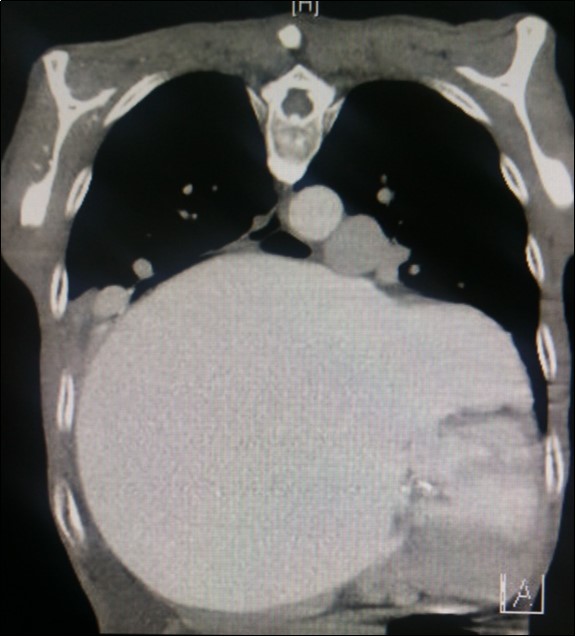

A dramatically dilated left atrium was seen on a TTE (see Figure 2a, Figure 2b, Figure 2c, and Figure 2d). Severe mitral stenosis with associated regurgitation was evident, with a mean gradient across the valve of 11mmHg and a hyperdynamic left ventricle. The left atrial volume measured by Simpson’s biplane method (see Figure 2c) was 2108mL, or 1548.5 ml/m2, based on height 1.55 metres and weight 44 Kg. Normal left atrial volume in a woman is 16 - 34 ml/m21. The computed tomography scan (CT) chest AP view (see Figure 3) is also shown.

Figure 3.Computed tomography scan (CT) chest AP view, showing the extent of the left atrium filling the left and right hemithoraces.

Computed tomography scan (CT) chest AP view, showing the extent of the left atrium filling the left and right hemithoraces.